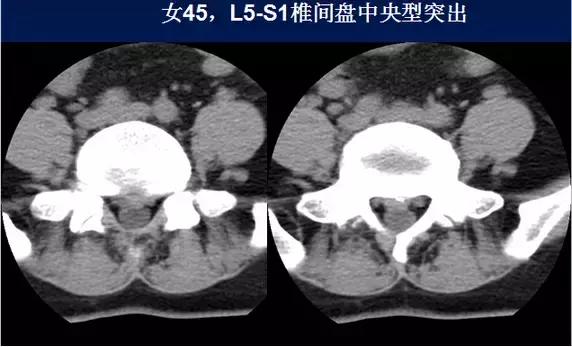

椎间盘突出:

⑴中央型:椎间盘影局限性超出椎体边缘,硬膜囊可受压,硬膜外脂肪间隙变窄、消失,可伴纤维环钙化。